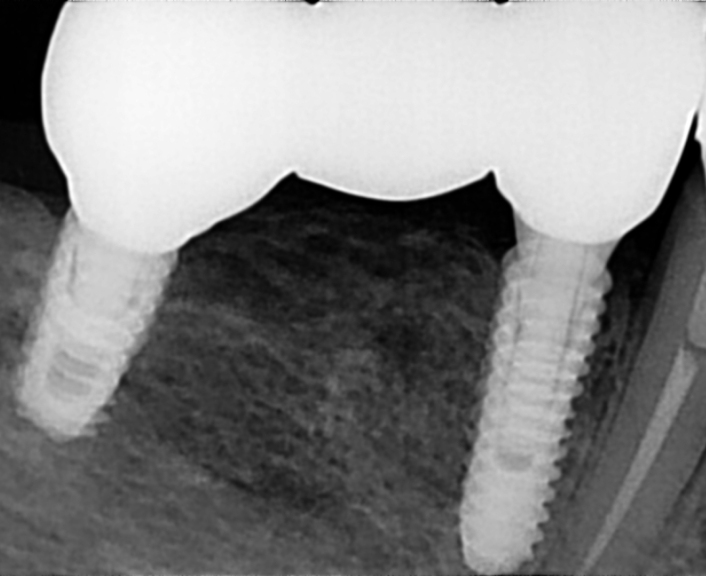

Regenerativni parodontološki zahvat kojim se kirurškim putem regenerirao infrakoštani defekt(parodontološki džep)